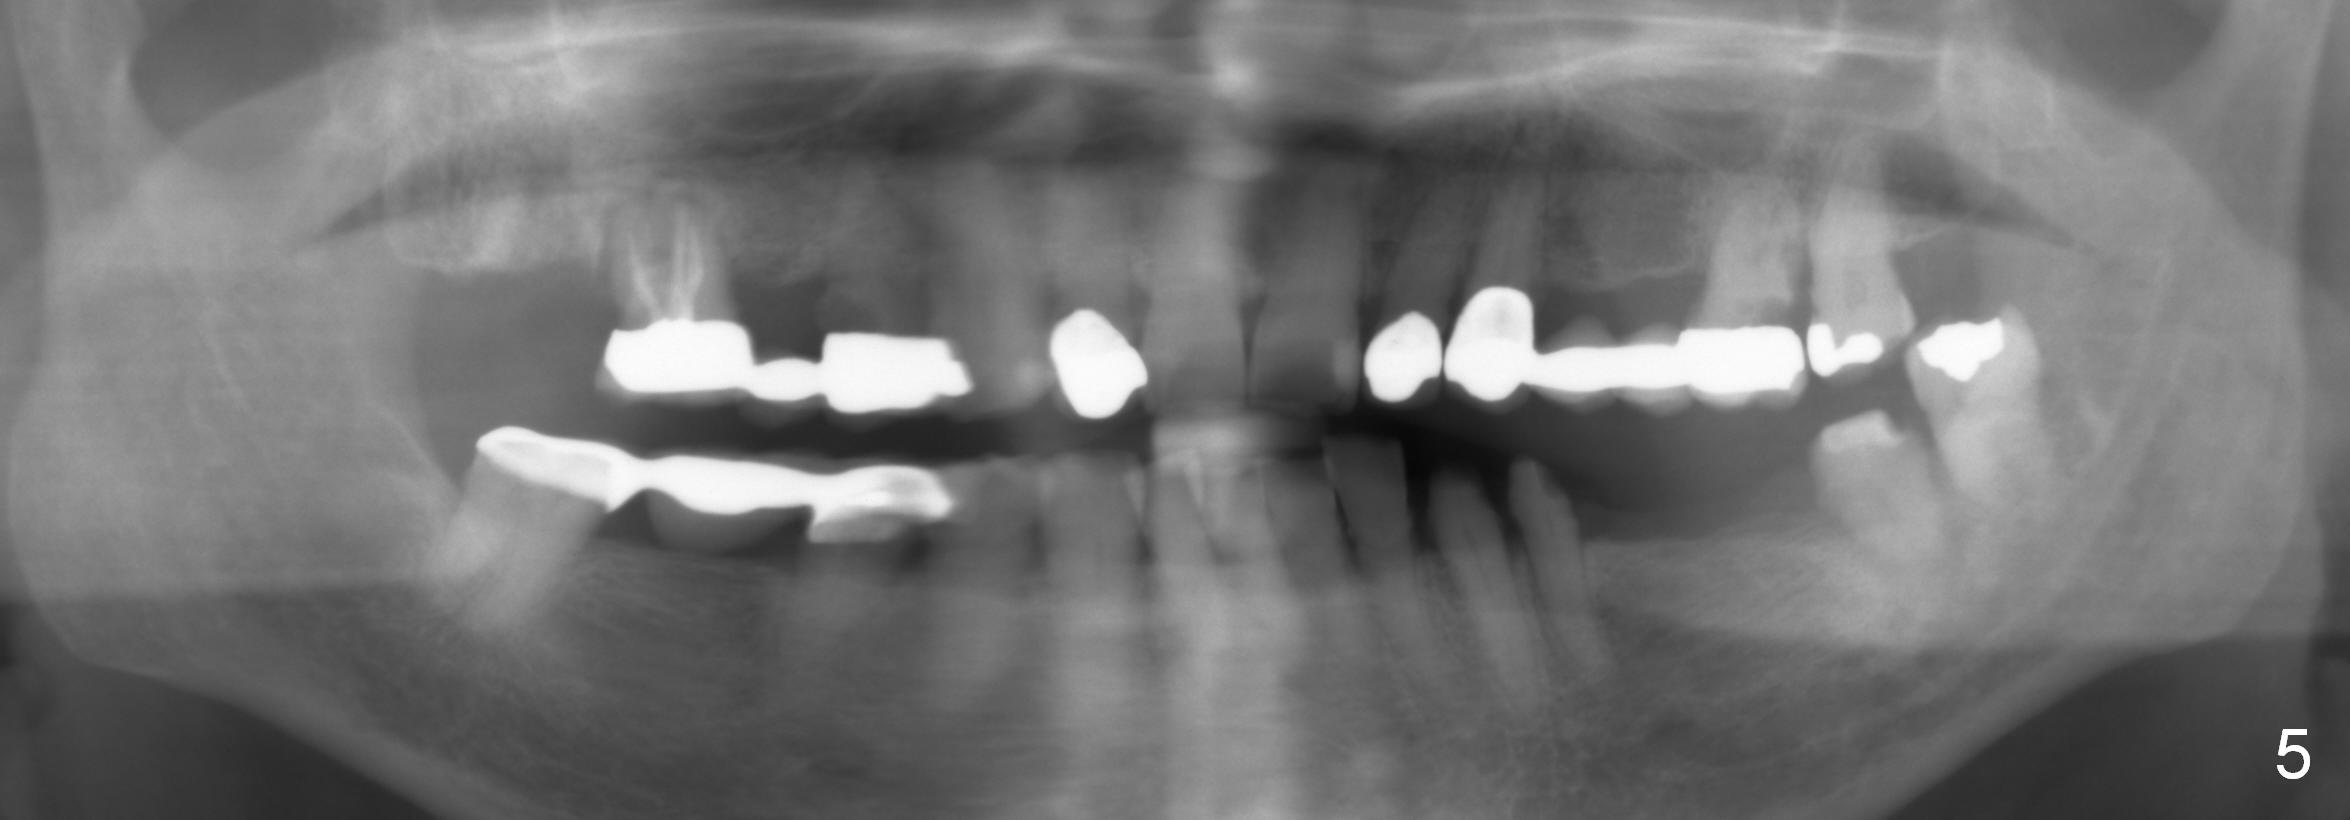

A 78-year-old lady (YT) has had poor dentition. The tooth #2 fractured 3 years ago (Fig.1). Now bone loss around the abutments for the bridge at #3-5 is more severe (Fig.2). There is an abscess palatal to the tooth #5. After extraction, the socket at #3 should be large (treated with 2% Xylocaine/1:50,000 Epinephrine). An extra wide implant is expected. Since there is more than 12 mm of bone in height (Fig.3), a UF implant is the most appropriate (6, 6.5 or 7x12 mm, Fig.4). The longest extra wide SM implant is 10 mm.